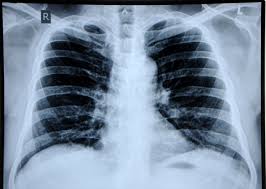

Asbestosis / Asbestos Related Diseases Asbestosis Pleural Plaques - Asbestosis is a process of diffuse interstitial fibrosis of the lung due to exposure to asbestos dust.. Asbestosis refers to later development of diffuse interstitial fibrosis secondary to asbestos fiber inhalation and should not be confused with other asbestos related diseases. Also called diffuse pulmonary fibrosis or pneumoconiosis, asbestosis is the leading cause of death for people exposed to asbestos. Asbestosis is a lung disease that develops when asbestos fibers cause scarring in your lungs. Looking for online definition of asbestosis in the medical dictionary? Though there is no cure, it can be managed with treatment.

The scarring restricts your breathing and interferes with the ability of oxygen to enter your bloodstream. The disease can get worse over time. When asbestosis occurs, it is typically 10 to 20 years after the initial exposure to asbestos. It may take many years after exposure to asbestos for the disease to develop. Asbestosis (genetic and rare diseases information center).

Dangers, testing, symptoms, and cancers what tests diagnose asbestosis? Sometimes complicated by pleural mesothelioma or bronchogenic carcinoma; Asbestosis is a chronic lung condition that develops after years of asbestos exposure. Asbestosis is a lung disease that occurs from breathing in asbestos fibers. The scarring restricts your breathing and interferes with the ability of oxygen to enter your bloodstream.

Also called diffuse pulmonary fibrosis or pneumoconiosis, asbestosis is the leading cause of death for people exposed to asbestos. Find out what causes asbestosis and what to do if an inspector suspects that a property has asbestos. Asbestosis is a typical pneumoconiosis (interstitial lung disease caused by inhaled inorganic the development and severity of asbestosis is related to the degree and duration of asbestos exposure. The scarring restricts your breathing and interferes with the ability of oxygen to enter your bloodstream. Asbestos exposure may also increase the risk of asbestosis (an inflammatory condition affecting the lungs that can cause shortness of breath, coughing, and permanent lung damage). Asbestosis is a chronic lung condition that is caused by prolonged exposure to high concentrations of asbestos fibers in the air. Dangers, testing, symptoms, and cancers what tests diagnose asbestosis? In most cases patients dont show any symptoms for. Asbestosis is a chronic lung condition that develops after years of asbestos exposure. Lung cancer (national cancer institute). Asbestosis is a process of diffuse interstitial fibrosis of the lung due to exposure to asbestos dust. Prolonged exposure to these fibers can cause lung tissue scarring and shortness of breath. While some people may not have serious symptoms, others may be.